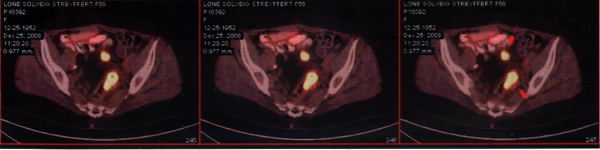

Sara小姐患卵巢癌,并发直肠转移癌、后腹膜腔淋巴结转移。PET-CT显示腹腔内多处有肿瘤活性。在新西兰共有5个医生为她治病,其中两位来自美国。由于以前她已接受卵巢切除,并做过全疗程化疗,因此进一步治疗遇到困难。2013年6月23日,Sara小姐来到广州中医药大学金沙洲医院肿瘤综合诊疗中心。她接受了综合治疗:手术—>切除直肠肿瘤—>对残存肿瘤作WB-1无创全身热疗—>化疗。2013年9月28日出院。

Sara小姐治疗前CT